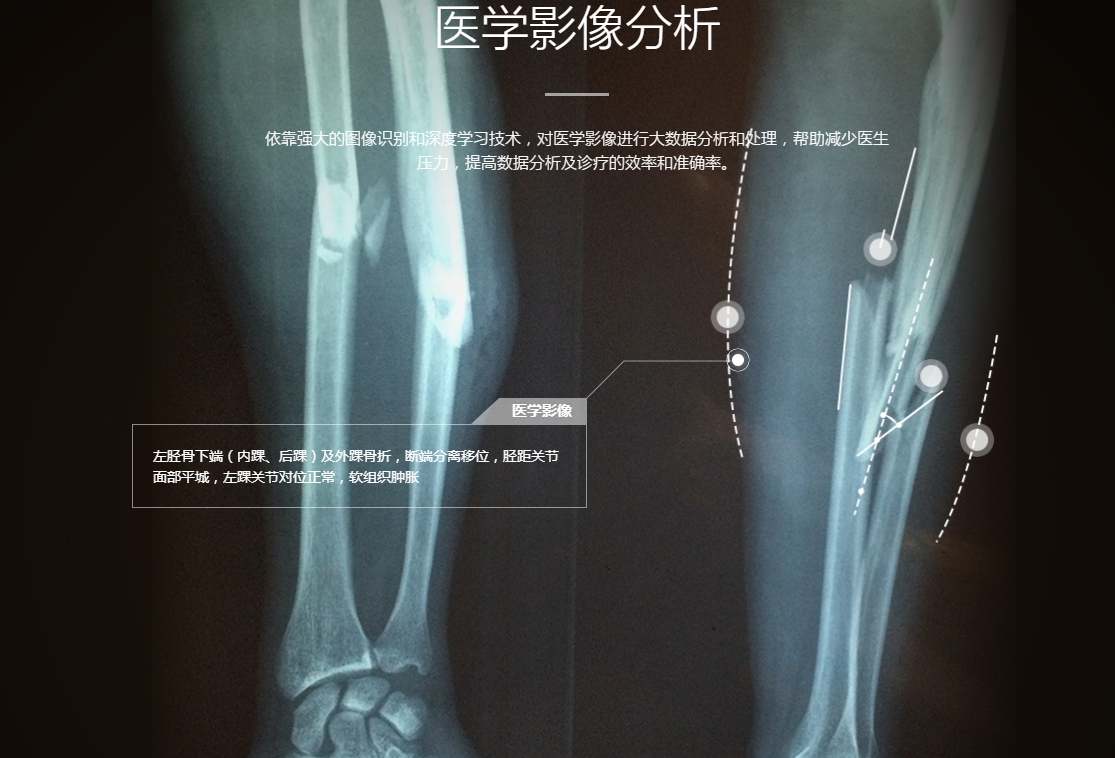

1、Enlitic 医疗诊断

Enlitic于2014年8月在三藩市成立,采用深度学习和图像分析帮助医生做出诊断并标记出医学图像中的异常,从而让医疗更加精确和更有效率。例如,Enlitic可以分析X光、核磁共振成像或CT扫描得到的医学图像,然后找出数据中的趋势或单个图像中的异常情况。

他的基本思考是,创造一个类似星际迷航三录仪一样的系统(不过可能无法便携),搜集有关特定病人的数据——从医疗图片、实验室检测结果到医生的便笺——让深度学习分析这些数据,做出诊断并给出治疗建议。这并非让机器替代医生,而是为其提供让诊断更加便利的工具。公司还将与诊所、医院以及其他医疗单位合作,分析算法,进一步精炼公司的技术。